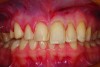

Fig 2. A preoperative retracted full-smile view. The restorations appear to be very “square” and “bulky.” The incisal embrasures are small, helping to make the teeth look uniform and square.

Figure 2

Figure 1 and Figure 2 show full-smile and intraoral full-arch views of the patient’s preoperative condition. The retracted full-smile image revealed disparate gingival heights over teeth Nos. 8 and 9. The proximal-facial line angles, particularly of the maxillary central incisors, were indistinct and rounded, contributing to a more “square” silhouette of the facial outline form. The maxillary anterior teeth appeared much larger in the cervico-incisal dimension with a dramatic decrease in height starting in the first premolar area (Figure 3). Esthetic harmony cannot always be achieved without addressing both hard and soft tissues and unfortunately, some clinicians “only see the white and not the pink.” The decreased height of the posterior teeth helped to contribute to the problem of the anterior teeth appearing too large. Prior to tooth preparation, a soft tissue correction was made with a diode laser (Picasso Diode Laser, AMD Lasers, amdlasers.com), which made the bulbous emergence profile of the existing veneer painfully evident. Because the patient had no second premolar due to extraction and orthodontics performed when the patient was younger, symmetry of the positions of the gingival margins was very important to the overall esthetics of the case. An imaginary line was drawn from the cervical height of contour of the maxillary cuspid to the gingival margin above the mesio-buccal root of the maxillary first molar. The gingival margin of the maxillary premolar needed to be on this line. If biologic width was violated, bony crown lengthening would be required (Figure 4). In this case, a closed-flap crown lengthening was performed with an ErCr: YSGG all-tissue laser (iLase® Plus, Biolase Technologies, biolase.com) to reestablish the proper 3-mm distance from the free gingival margin to the crest of bone. When healed, the new restoration would appear longer in the cervico-incisal dimension and gingival harmony would be achieved.